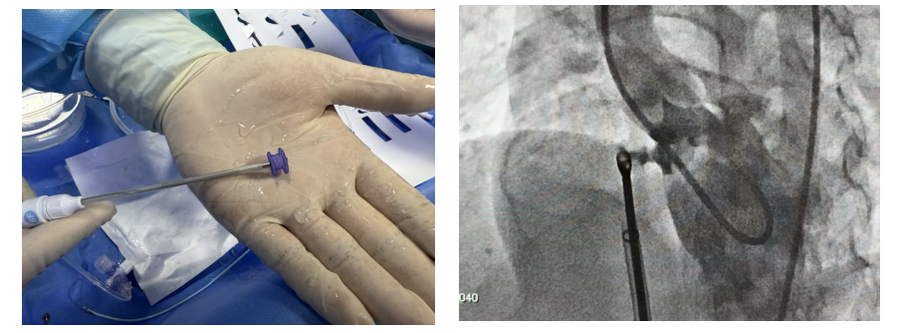

医院首次开展神经阻滞(局部麻醉)下介入手术——技术创新护童心 协作攻坚启新程

生命“守护者”就位! 山大附属儿童医院成功完成院内首例儿童长QT综合征ICD植入术